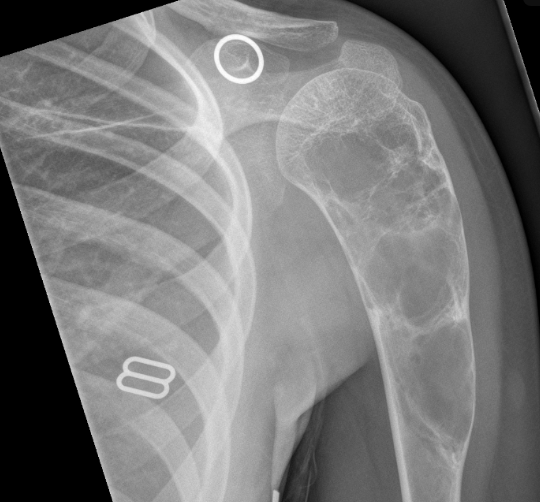

Aneurysmal Bone Cyst (ABC)